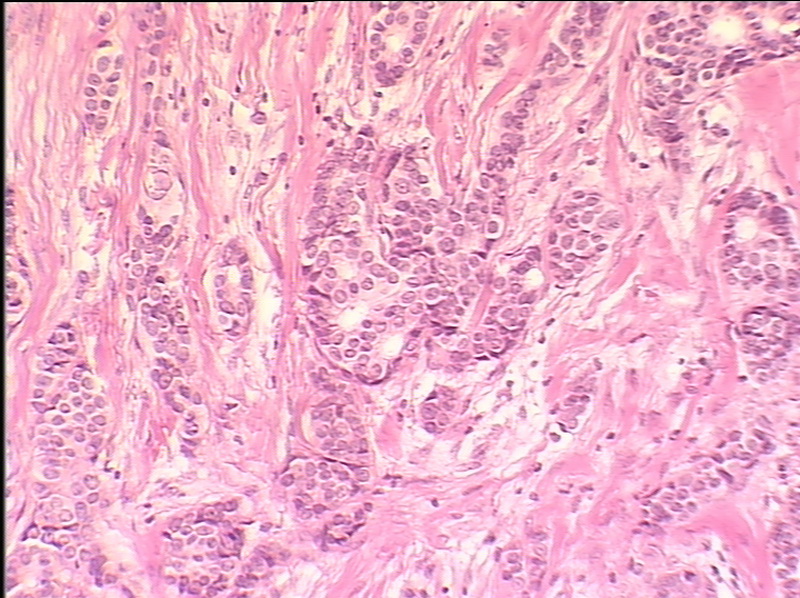

Исследование: микропрепарат молочной железы в медицине

Раздел: Снимки-откровения